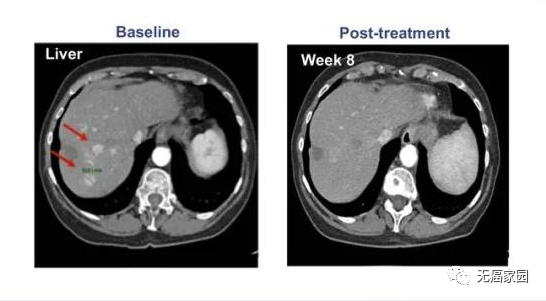

接下来,小编展示联合疗法中一个典型的成功案例,如图所示:治疗1~2个月后复查,肺部肿瘤完全消失,并且疗效已经保持了18个月。